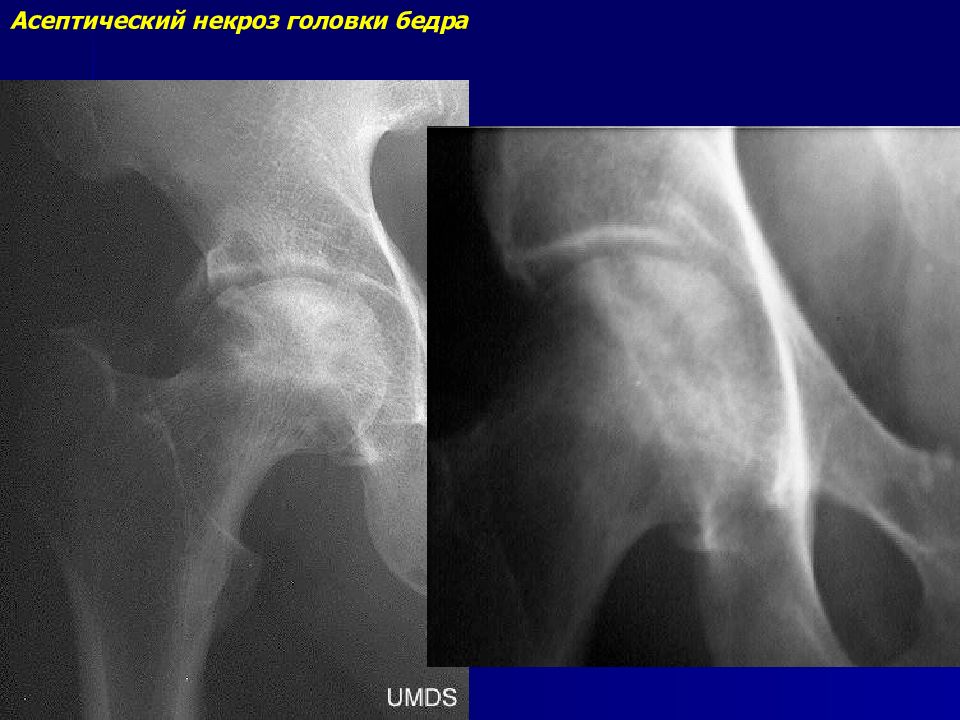

Некроз тазобедренного сустава: Фотографии и особенности лечения